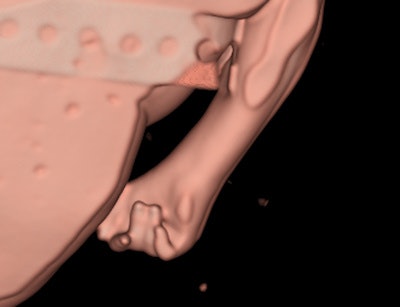

Six fetuses were initially scanned. Three fetuses had been delivered after death in utero, and three were from pregnancies terminated due to fetal abnormalities. In all but one fetus, the crown-rump and crown-heel length measurements determined on CT were within 6% of the autopsy measurements. There was quite poor correlation between CT and autopsy measurements of the fetal foot length and head measurements, probably due to fetal positioning; the foot can be more easily "straightened" during a direct examination.

Evaluation of the heart was poor on CT, as was expected in a noncontrast postmortem study, the authors reported. The heart was correctly identified as normal in fetus 5, but much of the heart could not be commented upon, and even the great vessels were difficult to confidently identify. Significant cardiac abnormalities were identified in fetuses 2 and 3 at autopsy. The diaphragm could be seen to be intact in four of the fetuses at CT, and was intact in all fetuses at autopsy.

The liver and spleen were identified in the correct position in four fetuses, and were not able to be assessed in two fetuses on CT. The kidneys proved very difficult to identify due to the absence of intra-abdominal fat. In the three fetuses that were identified on CT, the kidneys were normal at autopsy. The kidneys were not identified in fetus 4 on scanning, and at autopsy the renal parenchyma was multicystic dysplastic in nature and horseshoe in morphology. The gallbladder and pancreas were not reliably seen in any fetus on CT.